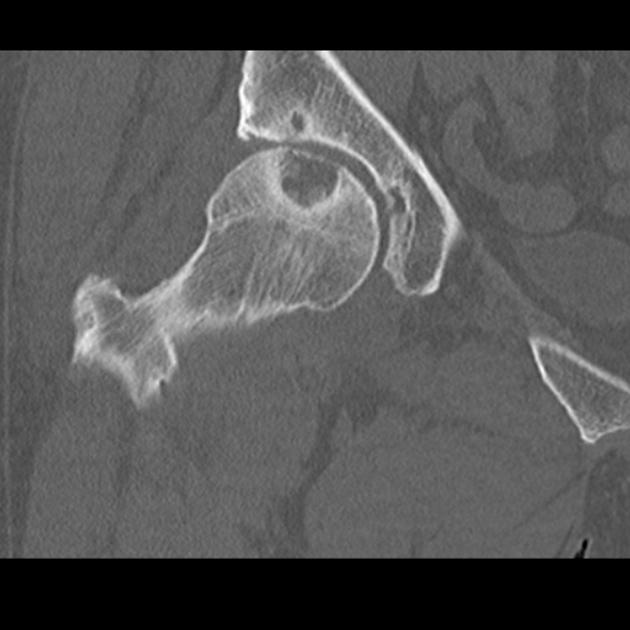

- На необходимость МРТ или КТ указывают наличие выраженной боли, ограничения подвижности в тазобедренном суставе. Также основание для выполнения диагностики – отсутствие изменений на рентгенологическом снимке. Благодаря методам удается нивелировать один из важных ограничительных моментов классической рентгенографии – эффект суммации. Изображения, получаемые по методикам лучевой визуализации, позволяют оценить состояние суставной ткани, мягких тканей околосуставного пространства.